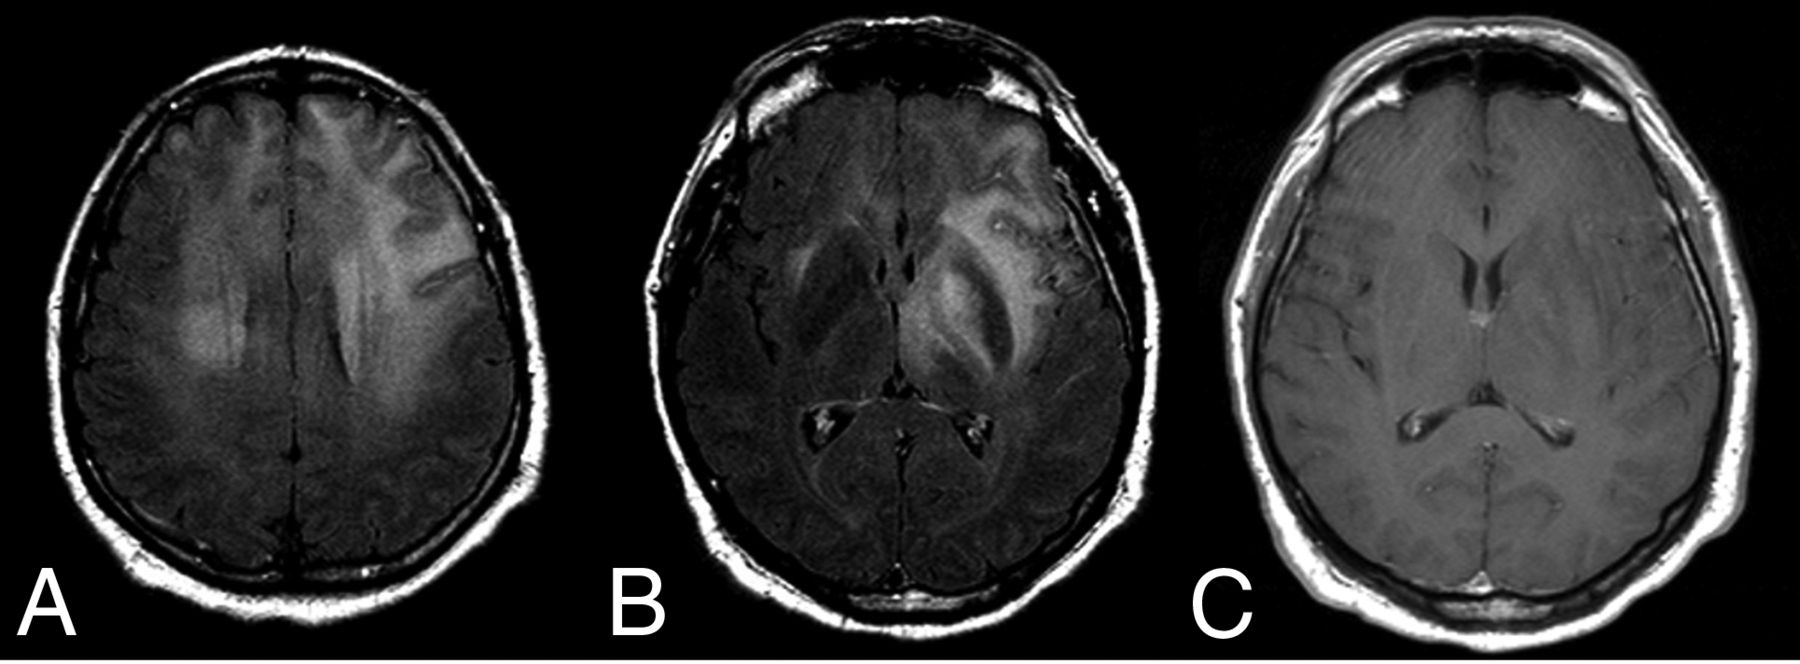

A–C: Primary DLBCLs of the CNS, EBV-negative, with imaging signs of central necrosis (A) and tumoral hemorrhage (B and C). D–G: DSC-PWI features of a left frontal primary DLBCL of the CNS, EBV-negative (D). Low-to-intermediate CBV on noncorrected (E) and corrected (F) color maps. Characteristic lymphoma DSC-PWI time-intensity curve morphology with ascending-part of the curve recovering signal intensity far above the baseline (high PSR) (G).

Regarding quantitative imaging techniques beyond DWI, 1H-MR spectroscopy and DSC-PWI, included in consensus recommendations for imaging CNS lymphoma,16 have shown promising results for presurgical diagnosis. Attention must be paid to pulse-sequence parameters (TE, TR, flip angle), prebolus usage, and leakage corrections for DSC-PWI, but in general terms, this tumor shows low-to-intermediate CBV, a high percentage of signal recovery (PSR), and characteristic time-intensity curve morphology.7,17,18 Lower CBV values in lymphomas have paradoxically been related to a worse prognosis of survival.19 1H-MR spectroscopy can also reinforce a presurgical suspicion in basically 2 ways: Short TE depicts much lower mIns (described as a glial marker) than that associated with enhancing non-necrotic astrocytoma (ie, grade 3), and long TE shows much lower mobile lipids (associated with necrosis) than glioblastoma or metastasis (Fig 2).20